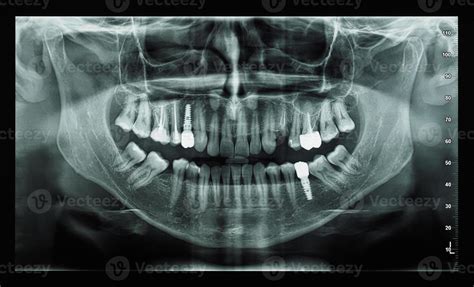

Es habitual que algunos adultos mantengan dientes de leche. Lo primero que hay que hacer es realizar una radiografía (ortopantomografía) para ver qué está pasando. En ella veremos si detrás del diente de leche hay o no un diente definitivo. Dependiendo de si existe o no estaremos ante una situación u otra.

Radiografía ortopantomografía.